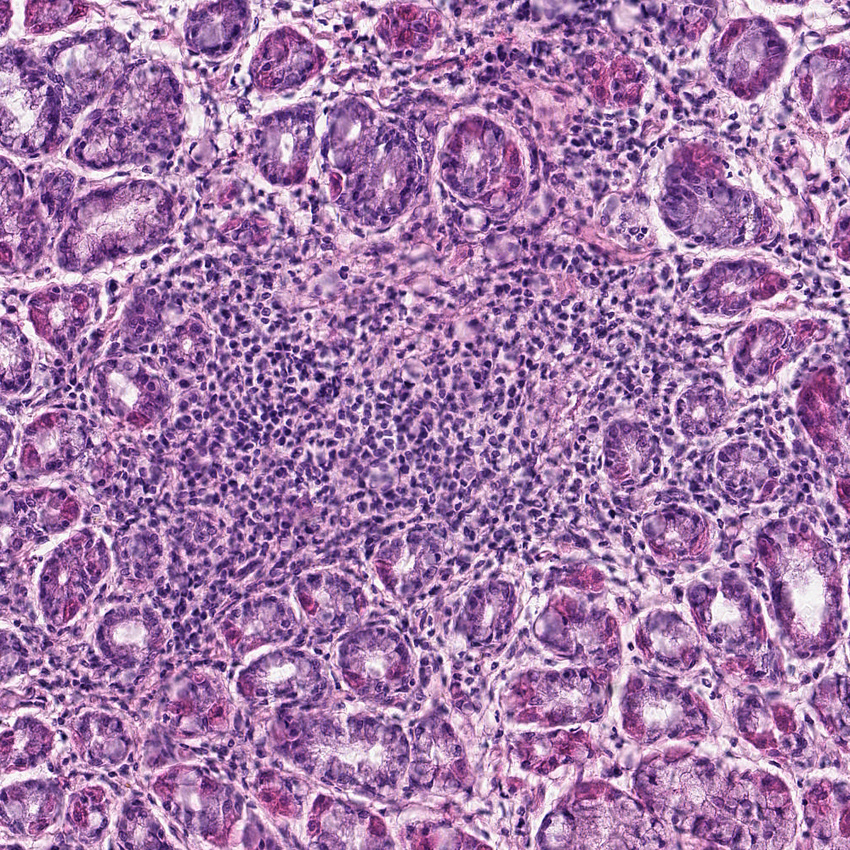

Cell types%

Glandular cells:

50

Smooth muscle cells:

10

Other cell types:

40